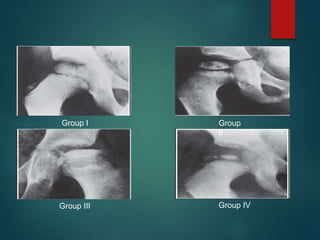

Catterall classification

 Group I: Only anterior portion of epiphysis

affected

 Group II: More of anterior segment involved;

central sequestrum present

 Group III: Most of the epiphysis sequestrated,

with unaffected portions located medial and

lateral to central segment

 Group IV: Entire epiphysis sequestrated

Group I Group

II

Group III Group IV